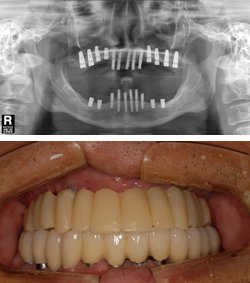

| ◇시술 후 |

서울그린치과병원 홍순창 원장은 “최근 등장한 무치악 임플란트는 시술은 20개 이상의 임플란트를 한 번에 심을 수 있어 치아가 전혀 없는 무치악 노인들에게 안성맞춤인 시술로 평가받고 있다”고 설명한다. 통증 및 출혈을 줄이고 치료 기간도 단축되어 환영받고 있는 것.